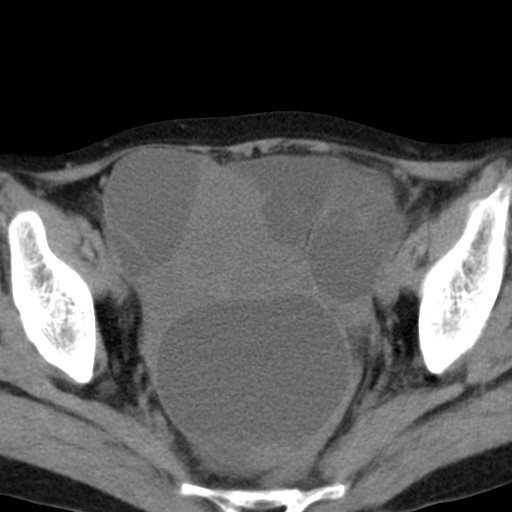

女,70,腹部间断性胀痛三月余

子宫宫腔及双侧附件积液,原因?

考虑卵巢囊腺瘤,不排除囊腺癌。

考虑卵巢囊腺瘤或囊腺癌。实质成分太多,考虑后者可能性大.

双侧卵巢粘液性囊腺癌,不多赘述。

考虑卵巢囊腺瘤;囊腺癌不能排除(理由:病人年龄较大,病灶外形欠规整、囊实相间,实性成分较多均支持囊腺癌)。要是能听听九目段老师的点评就好了!

年龄较大,囊实相间,实性成分较多均支持囊腺癌。